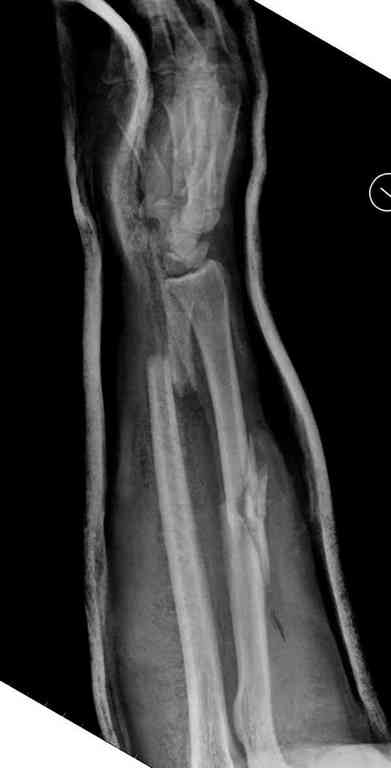

Отечность в зоне фиксации является противопоказанием к открытому методу. Для профилактики осложнений с фиксацией можно повременить применением стабилизирующего наружного фиксатора. Фиксатор восстанавливает длину конечности, облегчает в будущем репозицию и создает благоприятные условии для спадения отека. Также позволяет экономить средства, вместо дорогого стационара больной может находится на амбулаторном наблюдении. Появление симптома "skin wrinkle test" (морщинки) подскажет о готовности кожного покрова для окончательной операции на костях.

Множественная огнестрельная травма конечностей, перелом костей предплечья, фиксация в первые часы и дефект мягких тканей, мероприятия по закрытию...